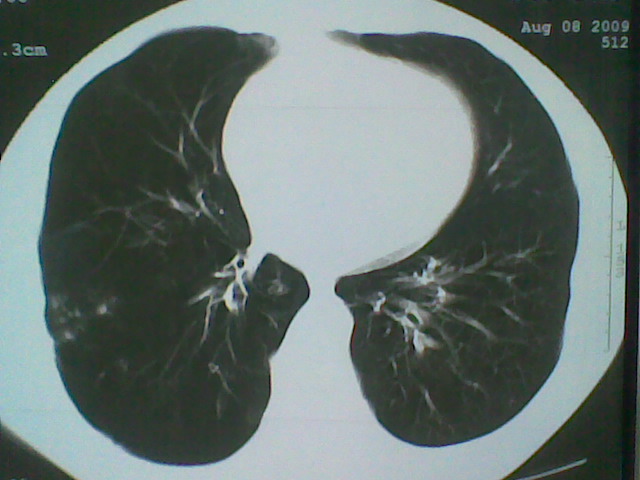

标题: CT21512:支扩伴感染? [打印本页]

标题: CT21512:支扩伴感染?

患者女。咳嗽数天,咯血半天。

我们报的是支扩伴感染?